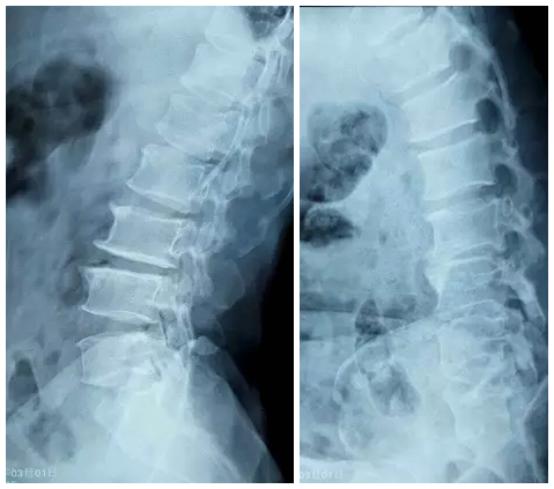

正侧位X片